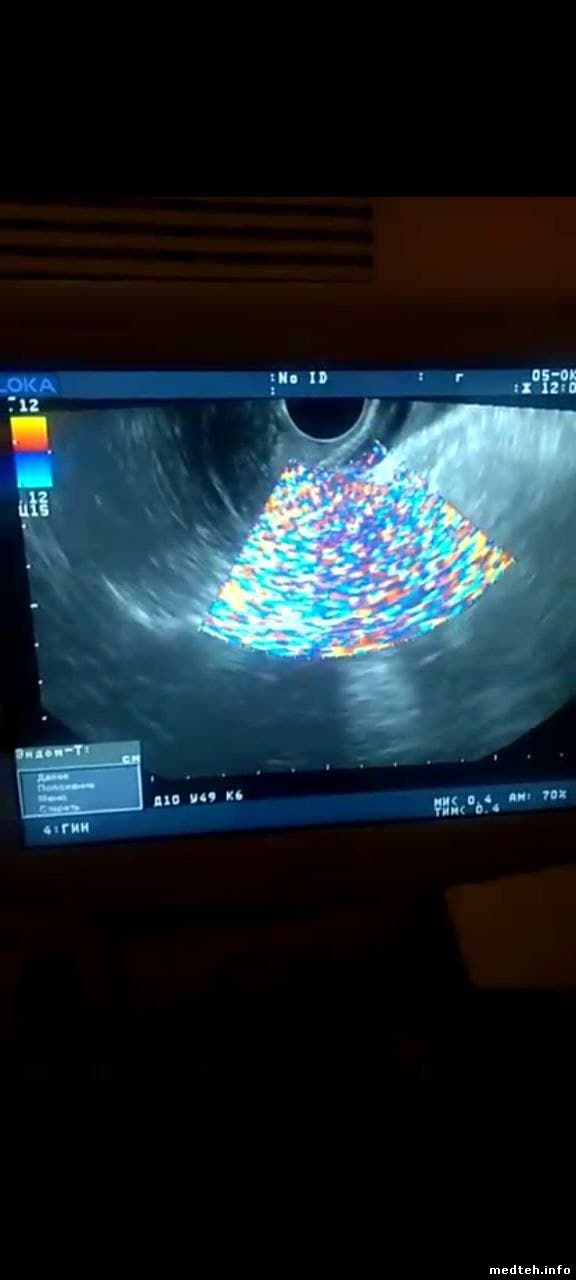

Проблема с УЗИ аппаратом - сильные помехи появились. Разбирал, чистил. Нашёл на мат.плате встроенного ПК вздутые кондёры, поменял.

Шум на всех датчиках. Появляется либо во время обследования, либо при увеличении усиления. Иногда всё работает нормально, но редко.

4445197.jpg (47.5 Kb)